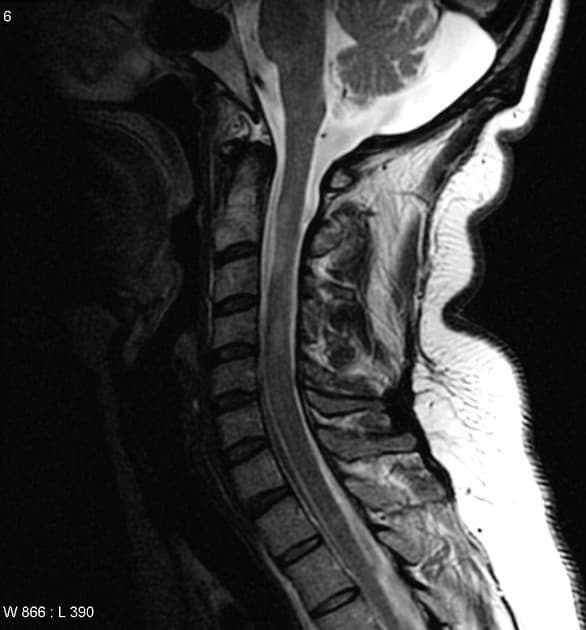

Sagittal FLAIR

Chụp cộng hưởng từ (MRI) cho thấy các đặc điểm điển hình của bệnh xơ cứng rải rác. Ngoài ra, một số tổn thương có tín hiệu tăng trên hình ảnh T1 (T1 hyperintense).

- Các tổn thương rải rác, dạng vệt hoặc hình tròn, tăng tín hiệu trên hình ảnh khuếch tán (diffusion-weighted imaging), khu trú chủ yếu ở vùng chất trắng quanh thất (periventricular white matter), chất trắng ở bán nguyệt (juxtacortical white matter), thân gai thị – giao thoa thị giác (optic radiation – optic chiasm), và thân não (brainstem) – phù hợp với đặc điểm của xơ cứng rải rác (multiple sclerosis).

- Thể chai (corpus callosum) có tổn thương dạng dải ngang (Dawson's fingers) – đặc trưng của xơ cứng rải rác (multiple sclerosis).

- "Dawson's fingers là các tổn thương ở chất trắng quanh thất, định hướng vuông góc với não thất, đặc trưng cho xơ cứng rải rác."